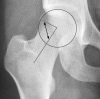

Femoroacetabular impingement syndrome (FAIS) is characterized by premature contact of the femur and acetabulum during hip motion. Morphologic variations of FAIS present as either aspherical femoral deformity (cam femoroacetabular impingement) or overcoverage (pincer femoroacetabular impingement) or both. Patients with FAIS often describe discomfort with hip flexion, adduction, and internal rotation. The use of hip arthroscopy to treat FAIS has risen substantially over the last 15 years. Given that one practice domain of the athletic training profession involves injury prevention and wellness protection, optimal FAIS treatment and management strategies warrant discussion. Sports medicine professionals often help patients with FAIS explore nonoperative exercise strategies and direct rehabilitation exercises for those who pursue surgery. Both approaches demonstrate key pillars of exercise program design, which include postural control, core stabilization, hip strength and motor control, and mobility. The purpose of this article is 2-fold: to present an overview of FAIS, including common diagnostic strategies, and commonalities in therapeutic approaches between nonoperative and postoperative rehabilitation for the treatment and management of patients with FAIS.